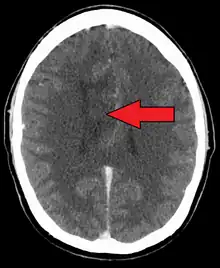

A oligoastrocytoma on CT

An X-ray computed tomography (CT) or magnetic resonance imaging (MRI) scan is necessary to characterize the anatomy of this tumor as to size, location, and its heter/homogeneity. However, final diagnosis of this tumor, like most tumors, relies on histopathologic examination (biopsy examination).[3]